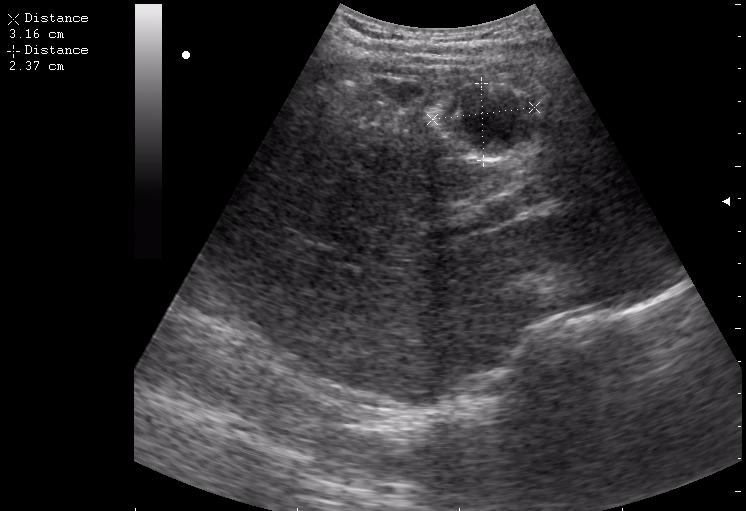

17-летняя девушка с множественными поражениями печени

нагноение остаточной полости

спустя 8 мес. после операции